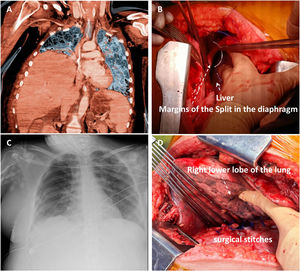

The clinical observation was made in a 43-year-old female patient admitted to our intensive care unit (ICU) after falling from a height. Her Glasgow Coma Scale was E1V1M4, and her vital signs were temperature of 35.9 °C, pulse rate of 135/min, respiratory rate of 32/min, and blood pressure of 91/50 mmHg. Physical examination revealed contusions in the left thoracic and abdominal region. Radiographic examinations revealed multiple right rib and pelvic bone fractures. Furthermore, CT of the chest and abdomen revealed elevation of the right hemidiaphragm, with a portion of the liver transposed into the right hemidiaphragm, emphasising a diaphragmatic defect (Fig. 1A). Cranial CT revealed no brain lesions.

(A) A preoperative computed tomography (coronal slice) scan of the chest and upper abdomen confirmed a right hemidiaphragmatic hernia, showing a liver in the right chest. (B) Image during repair surgery. A wide diaphragmatic defect showed protrusion of the liver through it. (C) Postoperative chest radiograph after surgical repair. (D) The surgical suture appreciated the width of the diaphragmatic tear.

Subsequently, the patient underwent a right posterolateral thoracotomy, and herniation of the liver and complete anteroposterior rupture of the diaphragm were observed in the thoracic cavity (Fig. 1B). After liver reduction, the diaphragmatic defect was repaired. The postoperative course was uneventful, and the patient was discharged 37 days later.